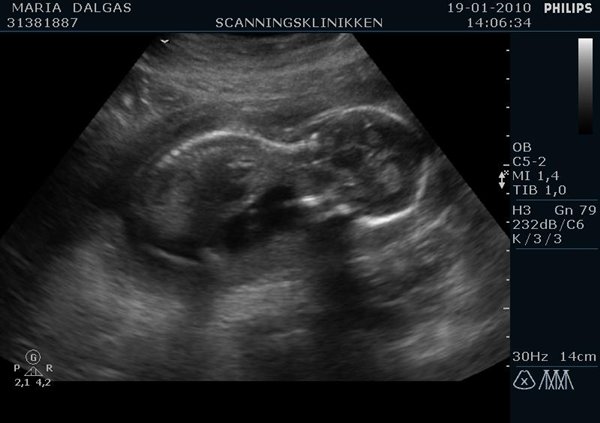

Ja så har man jo været til scanningen i dag og nøj hvor var det vildt I skal næsten selv gætte hvad det er ;P Her er billeder :

Er det en lille pige???

Jeg synes også jeg kan se skamlæber...

Men synes måske også det ligner en lille pige??

Jeg gætter også på en pige?

Jeg gætter på en pige, hvis det er imellem benene på det første billede.

Men umiddelbart hælder jeg mest til en pige.....???

Gætter på en pige , for det ligner det billede jeg så da jeg blev sacnnet med min datter i sin tid